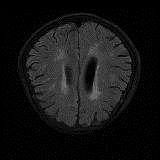

We obtain a subject-wise mean Dice score of 32.94% without any post-processing. By using a simple post-processing with erosion and dilation with filters, this number improves to 48.20% mean Dice score. In comparison, a similar study conducted by [3] consisting of a multitude of algorithms including AnoVAEGAN [4] and f-AnoGANS, obtained a best mean score of 27.8% Dice after post-processing by f-AnoGANS. Before post-processing the best method was Constrained AutoEncoder [8] with a score of 9.7% Dice. An exhaustive list is presented in Table 1. Figure 4 shows sample images of our results.

We obtain a subject-wise mean Dice score of 63.67% for the brain tumor segmentation. Utilizing a simple post-processing scheme of erosion and dilation with filter, we improve our mean Dice score to 68.01%. Figure 4 shows samples generated by our ASC-Net and Table 2 shows our before and after post-processing results. We attempted to apply f-AnoGANs [34] by following their online instructions and failed to generate good reconstructions as shown in Figure 5. The failure of AnoGANs in the reconstruction brings to light the issue with the regeneration based methods and the complexity and stability of GAN-based image reconstruction.